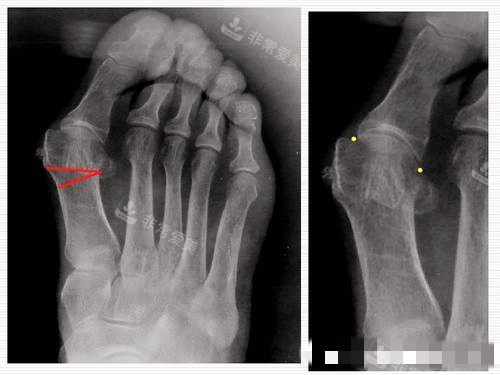

大脚骨X光片图片

首先是“更准一些检查”,除了常规的足部X光片,还会用3D足部扫描、压力测试等设备,详细评估拇外翻的角度、足弓形态、受力分布,甚至分析走路时的步态,找出问题根源;

大脚骨拍片

比如他们引进的小创口矫正技术,切口只有3-5毫米,用专用器械更准一些调整骨骼角度,不用打钢钉,术后第二天就能下地走,疤痕也几乎看不见——这点对爱美的女生太重要了!还有3D导航辅助系统,手术时能实时显示骨骼位置,避免损伤周围神经和血管,大大降低了并发症风险。